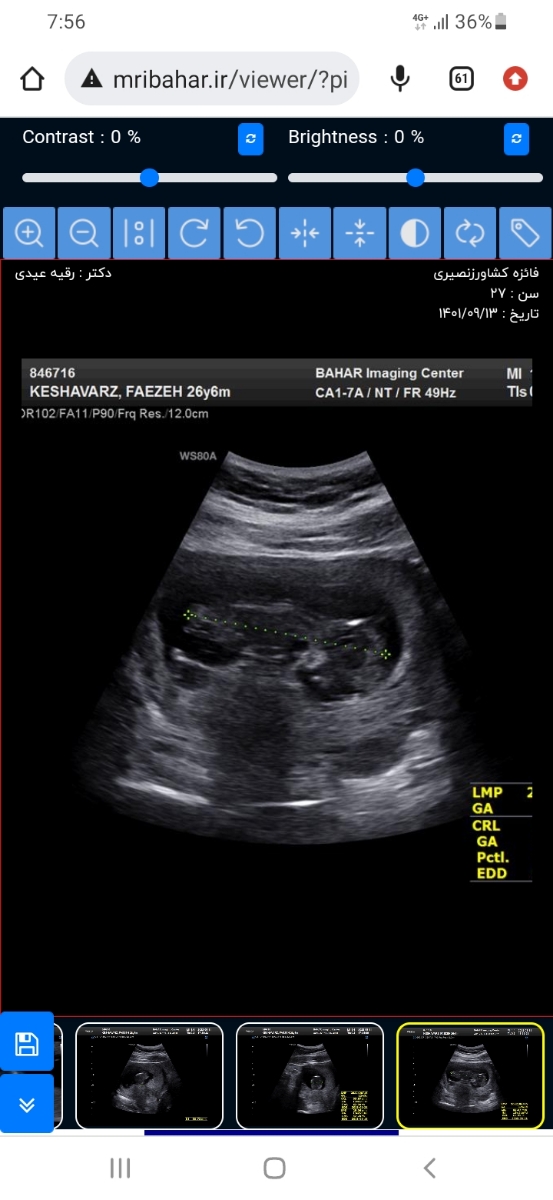

faezeh k

واسه منم ک عکس سونوش رو فرستادم اکثر خانوما گفتن پسره .

0

دوستان گفتن از برجستگی استخوان پیشونیش.

خیلی سخته تشخیص چون زوم نشده روش

ب نظرمنم هنوز قابل تشخیص نیست